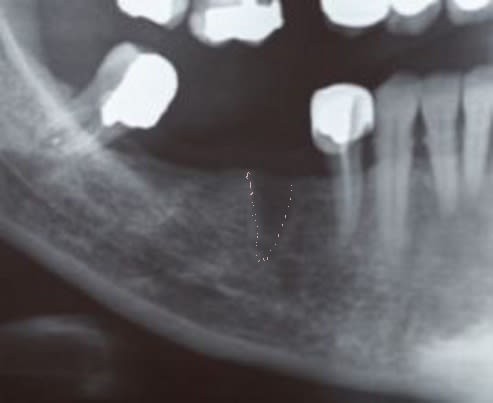

Motif de la consult : la 37 est sensible , enfin ça bouge , "j'ai une radio que "l'autre" dentiste ...(mon conf à 500m)".

je me doute bien que cette radio est une radio per-opératoire parce que on y voit nettement la trace du forage pour ton implant au niveau 46 (voir photo que je me suis permis de retoucher sans t'avoir demander la permission).

visiblement c'est un implant conique. peux tu nous en dire plus sur la marque ?c'est quoi ? Moly ? Mital-steel ?